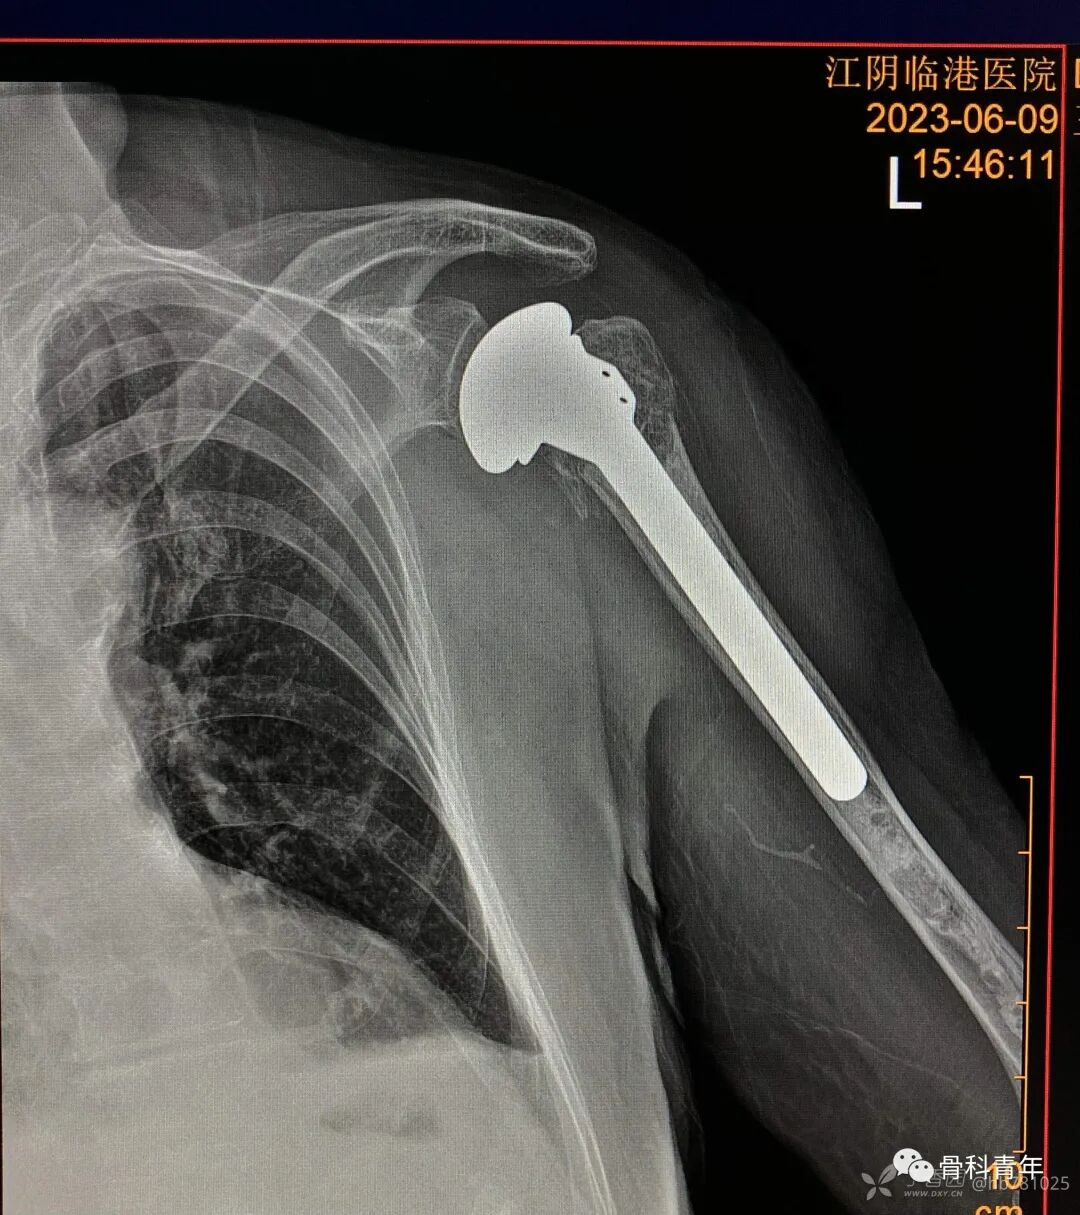

19.肩关节置换术